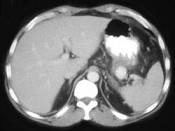

问题 男,36岁,反复剑突下胀痛5年,加重伴间断性呕血、黑便3年,有6年慢性胰腺炎病史,CT检查如图,最可能的诊断是 ( )

选项 A.脾血管瘤伴慢性胰腺炎 B.脾动脉瘤伴慢性胰腺炎 C.脾假性动脉瘤伴慢性胰腺炎 D.胰腺转移瘤伴慢性胰腺炎 E.胰腺癌伴慢性胰腺炎

答案 C